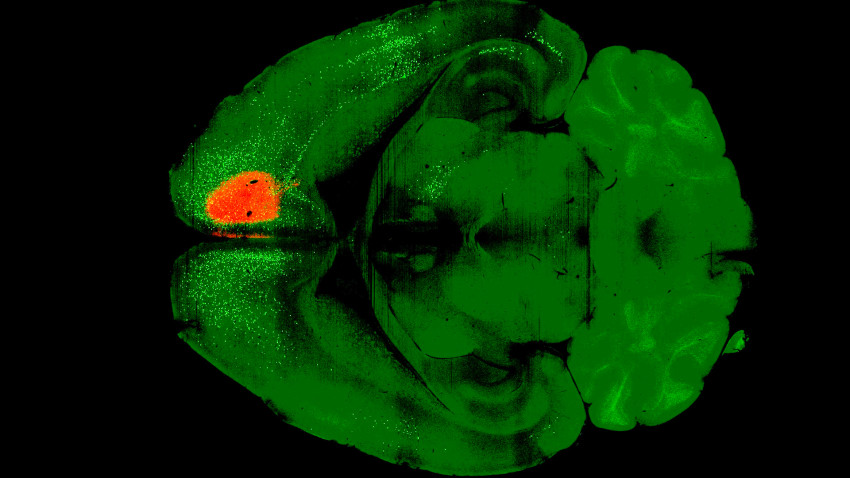

The research team administered a single dose of psilocybin to the frontal cortical pyramidal neurons of mice. After a day, they introduced a variant of the rabies virus capable of labeling connected neurons with fluorescent proteins. Following a week of incubation, the researchers imaged the brains of the treated mice and compared them with a control group that received only the virus.

The results highlighted that psilocybin significantly weakened recurrent connections within the cortex—feedback loops that often contribute to the ruminative thought patterns seen in depression. Kwan explained, “Rumination is one of the main points for depression, where people have this unhealthy focus and they keep dwelling on the same negative thoughts.” By diminishing these feedback loops, the research supports the idea that psilocybin can help rewire the brain in ways that disrupt these cycles.

Additionally, the study found that the sensory areas of the brain became more strongly linked to subcortical regions, enhancing the connection between perception and action. Kwan noted that the extent of rewiring was surprising, stating, “This is really looking at brain-wide changes. That’s a scale that we have not worked at before.”